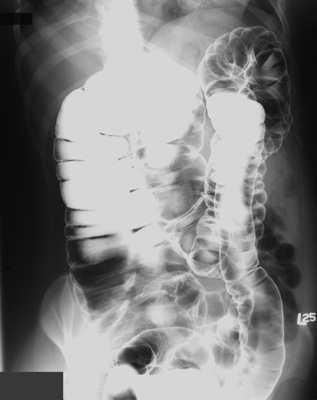

- PA view of colon to include rectum -

perpendicular central ray - 14" x 17" cassette